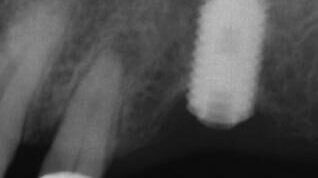

The patient presented on referral form Dr. S. for retrieval of a fractured abutment screw from a Noble Active 3.5 implant in the #29 site.